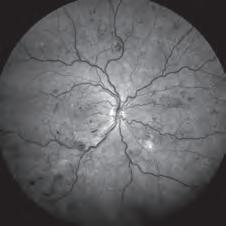

“So the best advice for now, whilst we await understanding of how and when we can access the new drug, is for clinicians to image the retina, ideally with autofluorescence, so that the rate of growth of the GA lesions can be determined, as this will be one factor to consider when advising on treatment.”

Clinicians, including optometrists, should also take this time to upskill in diagnosis GA secondary to AMD and to be familiar with lesion characteristics associated with fast growth, Prof Guymer said.

Citing the OAKS and DERBY trials, Prof Fung said the rate of GA expansion can be reduced by about 20% over two years, following monthly or every other month Syfovre treatment. This benefit appears to increase the longer a patient stays on treatment. But two aspects needed to be considered when selecting patients, he said.

“EYES WITH EXTRAFOVEAL, MULTIFOCAL LESIONS, A ‘DIFFUSE TRICKLING’ PATTERN AND ASSOCIATED RETICULAR PSEUDODRUSEN GROW THE FASTEST AND ARE MOST LIKELY TO BENEFIT.”

PROF ADRIAN FUNG

“The GA should have been documented to progress on macular imaging. Eyes with extrafoveal, multifocal lesions, a ‘diffuse trickling’ pattern and associated reticular pseudodrusen grow the fastest and are most likely to benefit from this treatment.”

For now, he encouraged optometrists to identify suitable patients and refer them to an ophthalmologist if they are motivated for treatment. Ophthalmologists should also keep a database of their AMD patients, and use imaging modalities such as fundus autofluorescence and en-face OCT to measure growth of geographic lesion size.